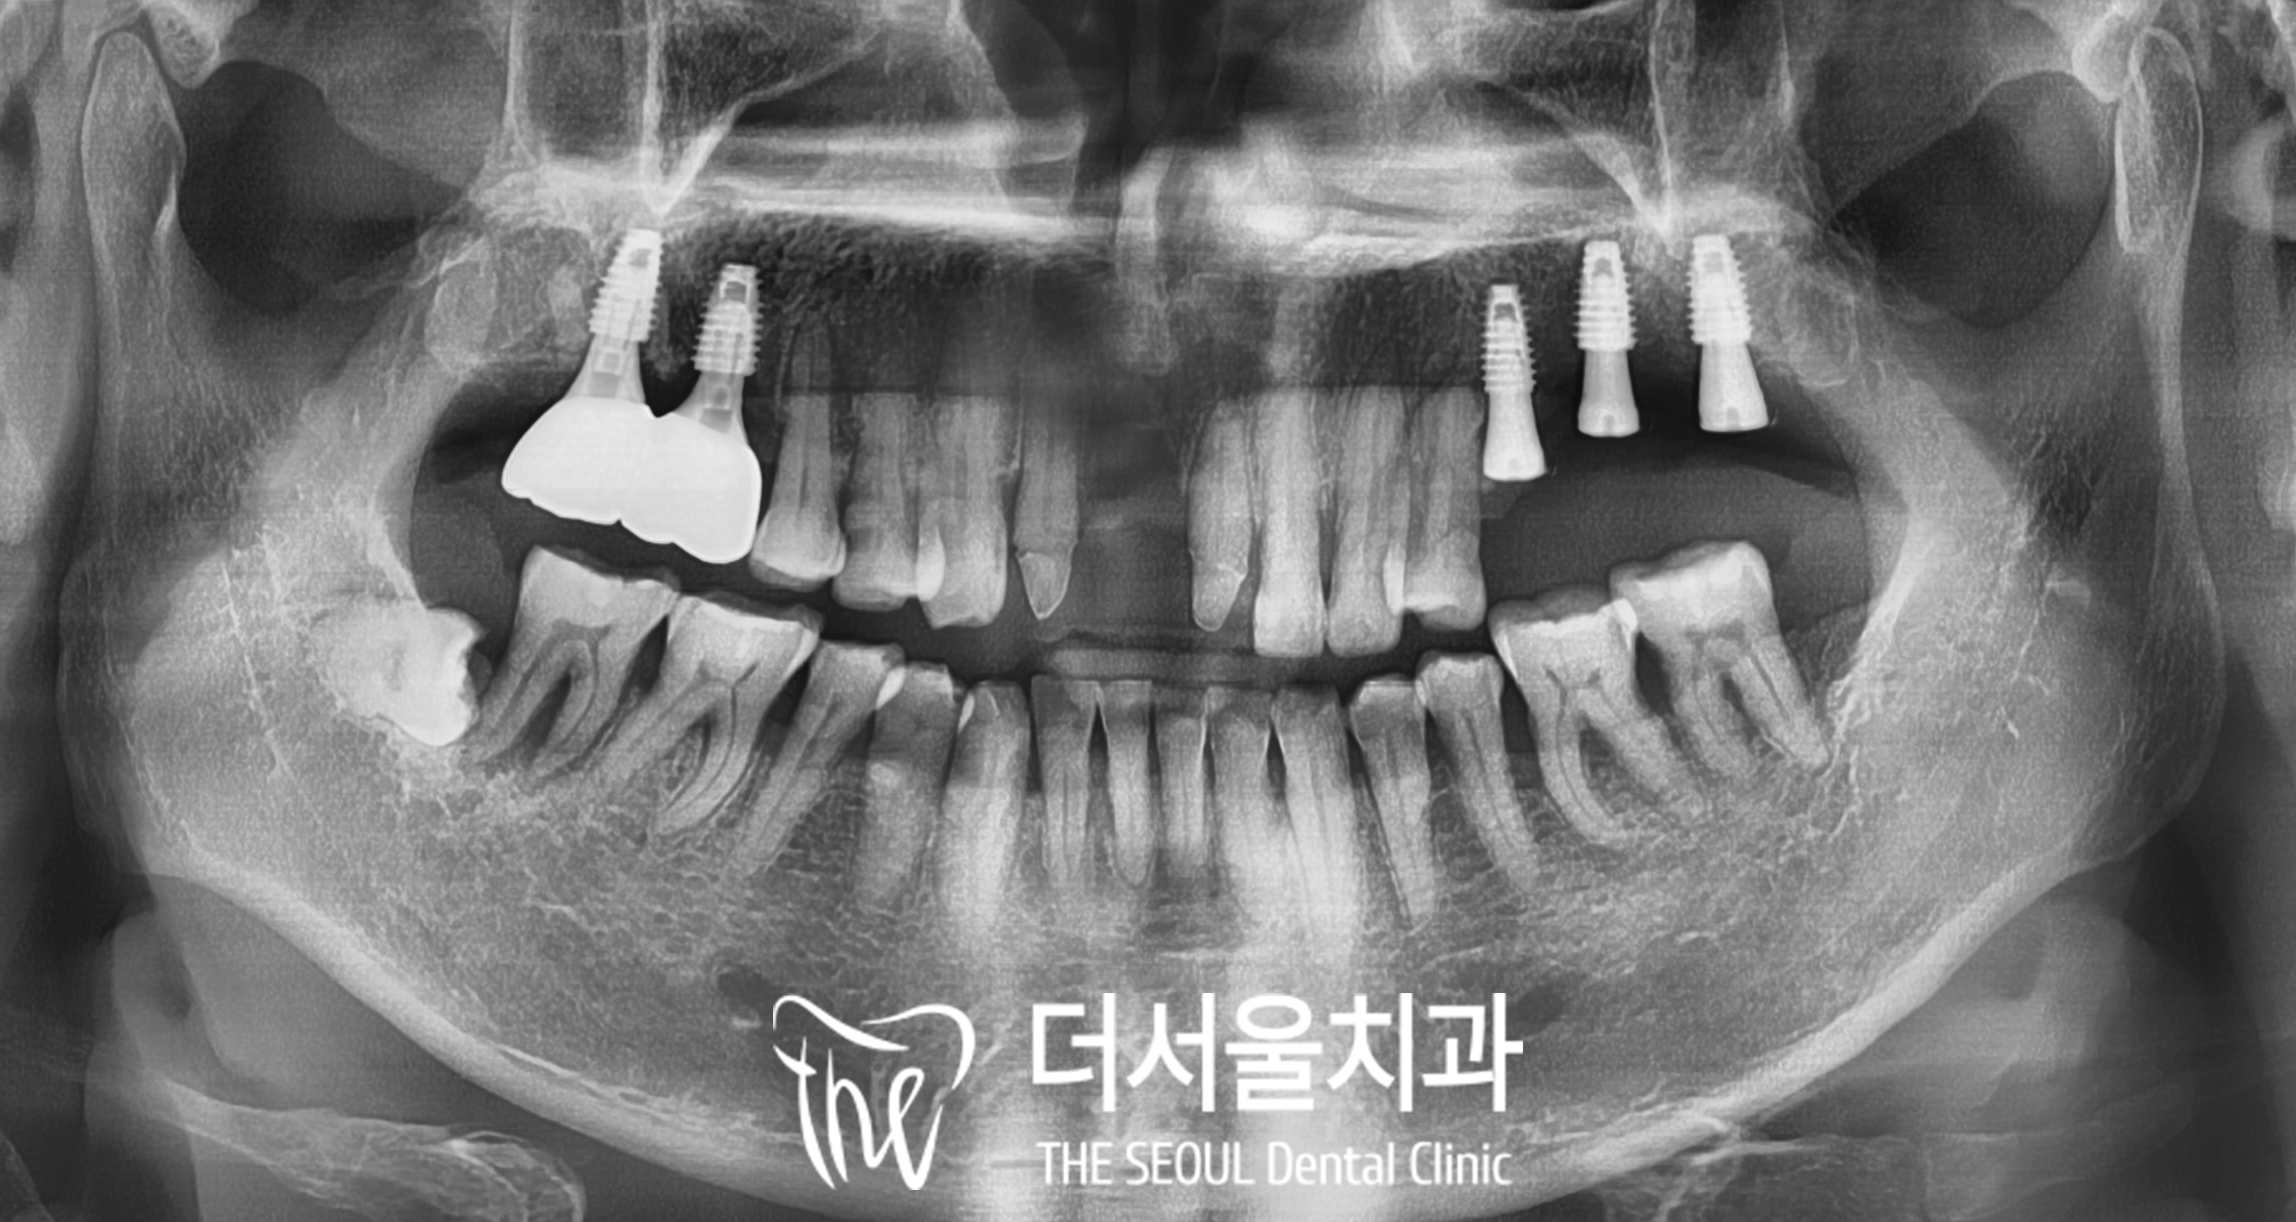

해외에서 내원하신 분으로

4년 전에 더서울에서 오른쪽 위 어금니

디지털 임플란트를 하고 나서

오랜만에 다시 찾아오셨습니다.

제가 해드린 상악 우측 구치부는

건강하게 잘 유지되고 있었으나

3. 디지털 임플란트

모란역 치과 에서는

위턱뼈에 픽스처를 심을 때

디지털 방식을 이용하고 있습니다.

다만 이때는

구강을 스캔 한 자료를 토대로

식립 위치와 방향, 각도를 고려하여

서지컬 가이드 제작해야 되는데요,

치조골 내에서 단단하게

잘 결합되는 것이 중요한 만큼

픽스처의 식립 위치를 철저하게 계산하고

이 케이스에서는

치근 부위에 염증이 심하여

내부를 깨끗하게 세척하고

4. 최종 보철 연결

디지털 임플란트와

환자의 뼈가 유착되기를

몇 개월 정도 기다렸다가

어느 정도 고정력이 확보되면

보철을 올려드립니다.